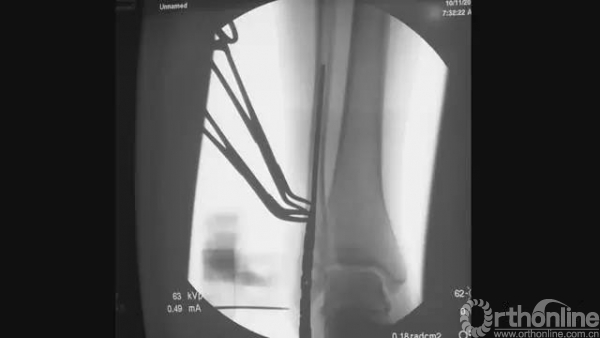

透视下将导针置于腓骨髓腔内

正侧位透视满意,均位于中心